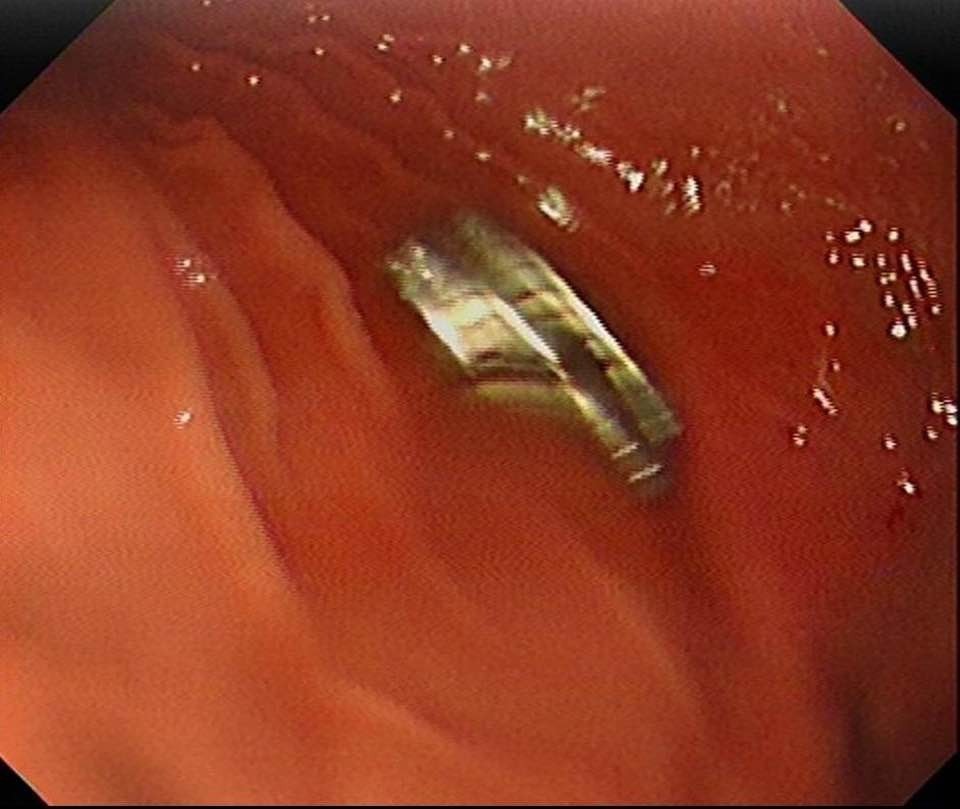

Daha sonra çocuk Elazığ’a sevk edildi. Fırat Üniversitesi Çocuk Gastroenteroloji Hepatoloji ve Beslenme Bilim Dalı Başkanı Prof. Dr. Yaşar Doğan, çocuk hastanın yemek borusuna yapışmış 19 mıknatısı endoskopik yöntemle çıkardı.

Mıknatıslar uzun süre yemek borusunda takılı kaldığı için yemek borusu ve mide girişinde zedelenmeler olurken, çocuğun sağlık durumunun iyi olduğu ve taburcu edildiği öğrenildi.